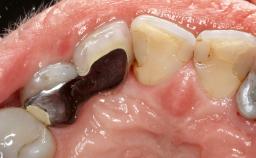

A 72-year-old female patient was referred to the specialist clinic with signs of peri-implantitis associated with implant 14. Two implants (sites 14 and 15) had been in function for three years. The patient was in good general health and was not taking any medication. She was a former smoker (12–15 cigarettes a day for 50 years) but had ceased smoking two years prior to implant placement. Her periodontal condition was stable, with no probing depths above 5 mm and a full-mouth plaque score (FMPS) of 35%.